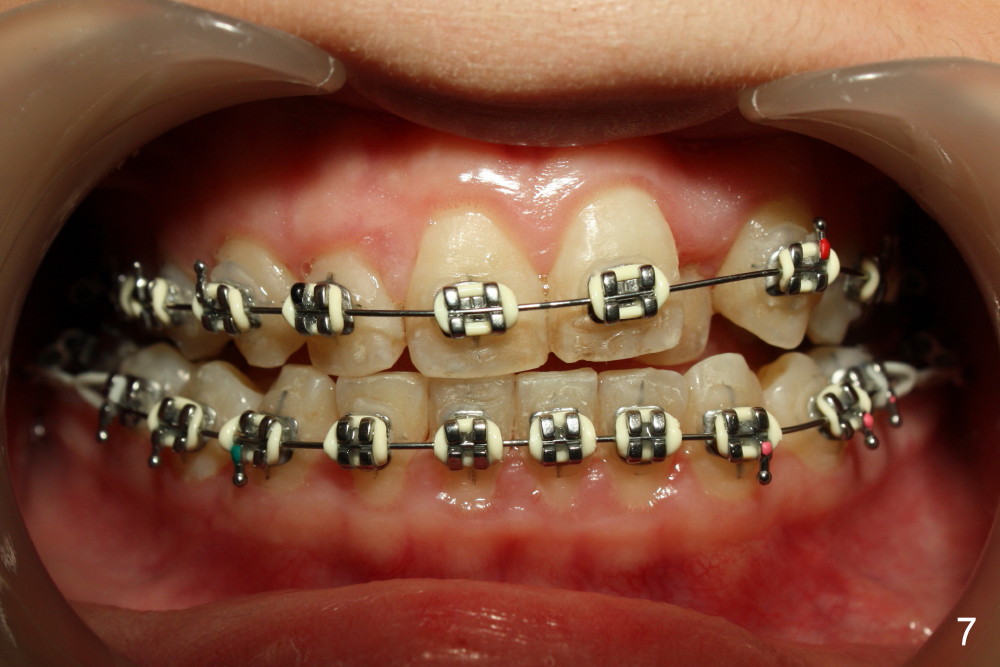

In one month, wires (.016 niti just installed) are straighter although there is slight open bite on the left (Fig.7, compare to Fig.5). It may be beneficial to ask the patient to use (next appointment) an elastic between L3,4s to reduce the open bite. Power chains are continuously used bilaterally between L5,6 (Fig.7,8).